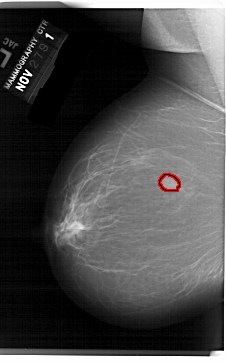

A_1519_1.LEFT_MLO

LEFT_MLO LINES 6871 PIXELS_PER_LINE 4276 BITS_PER_PIXEL 12 RESOLUTION 43.5 OVERLAY

FILE: A_1519_1.LEFT_MLO.OVERLAY

TOTAL_ABNORMALITIES 1

ABNORMALITY 1

LESION_TYPE MASS SHAPE OVAL MARGINS OBSCURED

ASSESSMENT 4

SUBTLETY 5

PATHOLOGY BENIGN

TOTAL_OUTLINES 1

BOUNDARY